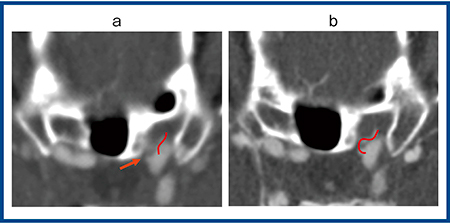

図2は,内頸動脈の眼動脈瘤疑いの症例だが,ADCT(a)では左内頸動脈の内側に眼動脈があり,その前方に突出した部分が認められ,動脈瘤ではないかと疑われた(→)。これをAquilion Precision(b)で撮影したところ,動脈瘤ではなく眼動脈が内側から分岐している正常構造を見ていたことがわかった(赤実線)。超高精細CTによって,従来であれば間違って診断しかねない病態についても正確に把握でき,偽病変を減らすことにもつながると期待される。

図2 内頸動脈眼動脈瘤疑い

a:ADCT b:Aquilion Precision